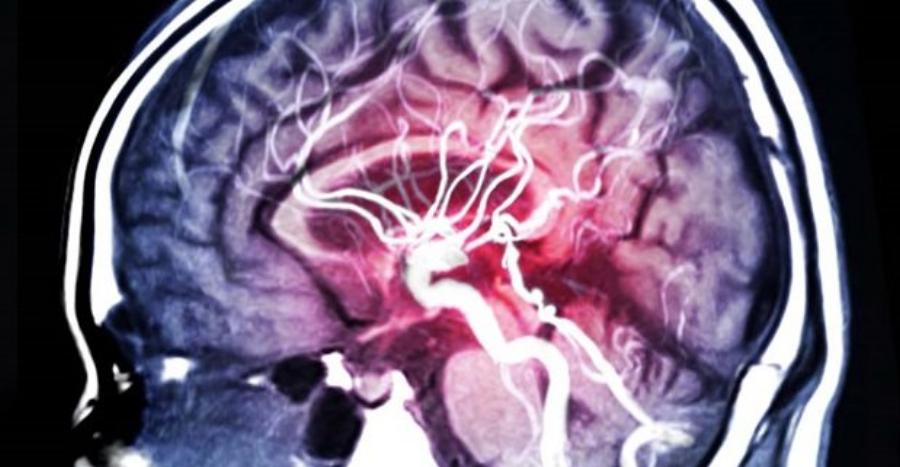

Το ανεύρυσμα εγκεφάλου μοιάζει με ένα μικρό μπαλόνι που μπορεί να «σκάσει» οποιαδήποτε στιγμή και η ρήξη του ανευρύσματος αποτελεί επείγουσα κατάσταση. Εάν το ανεύρυσμα έχει σχηματιστεί σε αιμοφόρο αγγείο του εγκεφάλου, η ρήξη συνεπάγεται ότι διαρρέει αίμα στους γύρω ιστούς.

Το ανεύρυσμα είναι ένα παθολογικό «φούσκωμα» σε μία από τις μεγάλες αρτηρίες του εγκεφάλου. Το «φούσκωμα» αυτό έχει σαθρά τοιχώματα, και κάποια στιγμή μπορεί να σπάσει. Λίγες φορές τα ανευρύσματα του εγκεφάλου οφείλονται σε λοιμώξεις, σύνδρομα ή άλλα αίτια. Στην μεγάλη πλειοψηφία των περιπτώσεων («σακκοειδή» ανευρύσματα) δεν υπάρχει εμφανής προηγούμενη νόσος υπεύθυνη για την δημιουργία του ανευρύσματος.